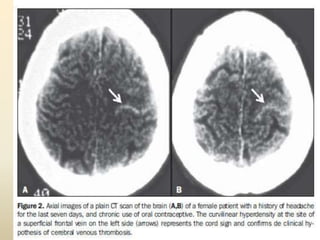

CT FINDINGS IN CVT

 Dense clot sign - Areas of thrombosis in sinuses

appearing as hyperdensities in unenhanced ct.

 Cord sign - Dense cortical veins-uncommon direct

sign of cvt in unenhanced ct.

Imaging: Cortical Vein Thrombosis